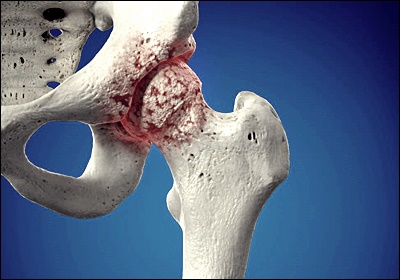

고관절은 우리 몸에서 가장 큰 관절 중 하나로, 대퇴골 머리와 골반의 비구가 만나는 부위입니다. 이 관절은 체중을 지탱하고 보행, 달리기, 점프 등 다양한 움직임을 가능하게 합니다. 고관절은 활액막, 연골, 인대 등으로 구성되어 있으며, 이들이 조화롭게 작용하여 부드러운 움직임을 가능케 합니다. 하지만 이러한 구조물 중 어느 하나라도 문제가 생기면 통증이 발생할 수 있습니다. 고관절의 정상적인 기능은 우리의 일상생활과 신체 활동에 매우 중요하므로, 이 부위의 건강을 유지하는 것이 필수적입니다.

고관절 통증의 원인은 매우 다양합니다. 가장 흔한 원인으로는 퇴행성 관절염을 들 수 있습니다. 나이가 들면서 관절 연골이 닳아 없어지면서 발생하는 이 질환은 점진적인 통증과 뻣뻣함을 유발합니다. 또 다른 주요 원인으로는 고관절 충돌 증후군이 있는데, 이는 대퇴골 머리와 비구 사이의 비정상적인 접촉으로 인해 발생합니다. 류마티스 관절염, 골다공증으로 인한 골절, 활액막염, 건염 등도 고관절 통증을 일으킬 수 있습니다. 때로는 요추의 문제가 고관절 통증으로 나타나기도 하므로, 정확한 진단이 중요합니다.